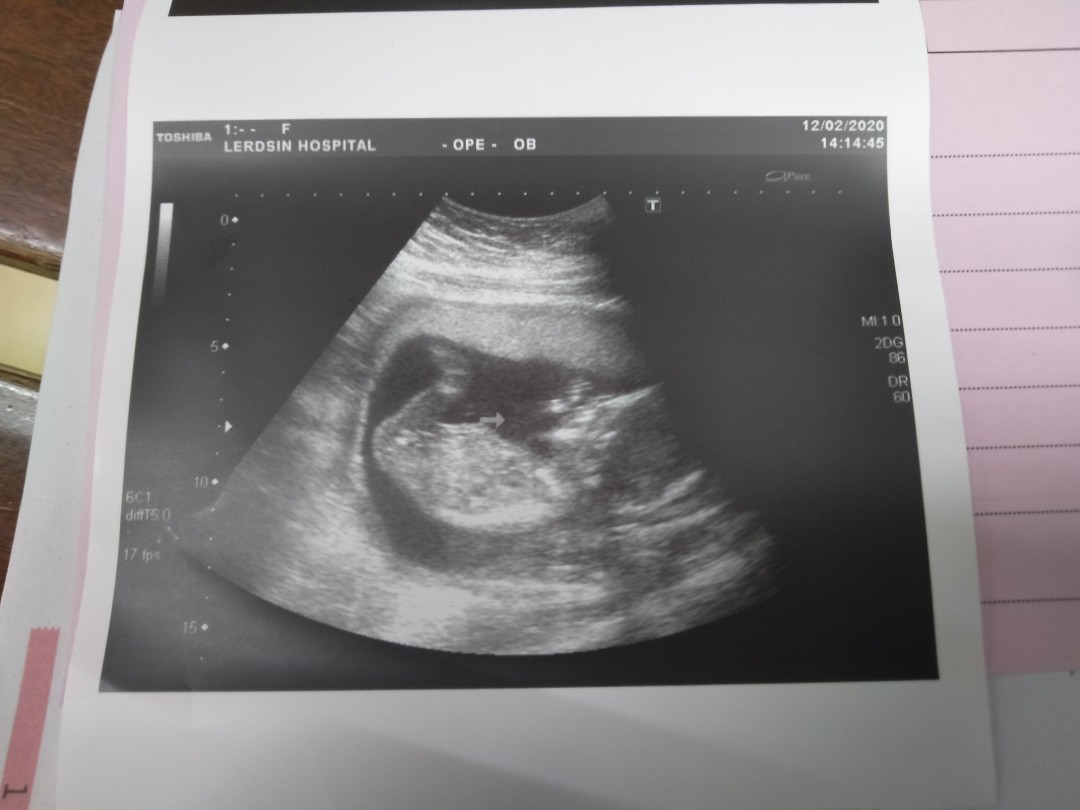

13วีค6วันค่ะแม่